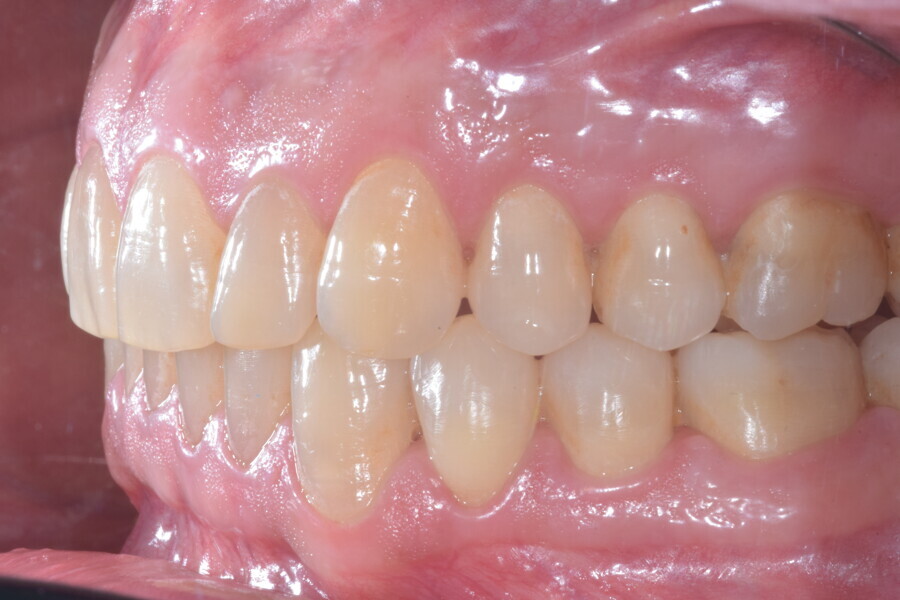

En raison de l’âge du patient, les aligneurs ont été changés tous les dix jours, dans le cadre d’un traitement d’une durée inférieure à six mois. À la fin de la première série d’aligneurs, un nouveau plan de traitement numérique comportant cinq autres aligneurs a été conçu, en vue d’améliorer l’intercuspidation des molaires sans élastiques. (Photos : Dr Alessandro Greco)

Le plan de traitement numérique (ClinCheck) avait prévu douze aligneurs pour l’arcade maxillaire et dix-sept pour l’arcade mandibulaire. Les objectifs du traitement visaient à combiner les mouvements verticaux d’extrusion des dents postérieures et les mouvements d’intrusion des dents antérieurs, au moyen de rampes d’occlusion, tout en utilisant des taquets d’extrusion pour assurer la désocclusion des dents postérieures et l’intrusion des dents antérieures inférieures, nécessaires au nivellement de l’arcade mandibulaire. La courbe de Spee a été nivelée et le profil plat ainsi que la position des lèvres ont été améliorés par une vestibulo-version des incisives supérieures et inférieures. Le plan avait prévu des élastiques de classe II pour faciliter la vestibulo-version des dents inférieures et les puissants contacts occlusaux postérieurs, avec une extrusion relative des dents postérieures. Une morphologie plus large de l’arcade et une intercuspidation idéale ont été obtenues par des mouvements de torque proches de 0° des dents latérales et postérieures supérieures. Aucune conception technique excessive n’avait été prévue dans le plan de traitement numérique. En raison de l’âge du patient, les aligneurs ont été changés tous les dix jours, dans le cadre d’un traitement d’une durée inférieure à six mois. À la fin de la première série d’aligneurs (Figs. 20–24), un nouveau plan de traitement numérique comportant cinq autres aligneurs a été conçu, en vue d’améliorer l’intercuspidation des molaires sans élastiques. La durée totale du traitement a donc été prolongée jusqu’à 7,5 mois puisque les aligneurs supplémentaires étaient changés toutes les semaines.

À la fin du traitement, on pouvait observer une relation de classe I des canines et des molaires, une légère augmentation de l’inclinaison des incisives supérieures (Ui-FH = 112°), une correction complète de l’inclinaison des incisives inférieures (IMPA = 97,09°) grâce à la vestibulo-version, et une légère amélioration de l’hypodivergence (SN-GoGn = 27°) résultant de l’extrusion relative des dents postérieures, et de l’utilisation d’élastiques de classe II — petite variation (1°) très intéressante compte tenu de l’âge du patient (Figs. 25–35). La ligne du sourire était harmonieuse et correspondait à une relation idéale entre les incisives supérieures et la lèvre inférieure. Le sourire avait été élargi grâce au contrôle du torque des segments latéraux et postérieurs.